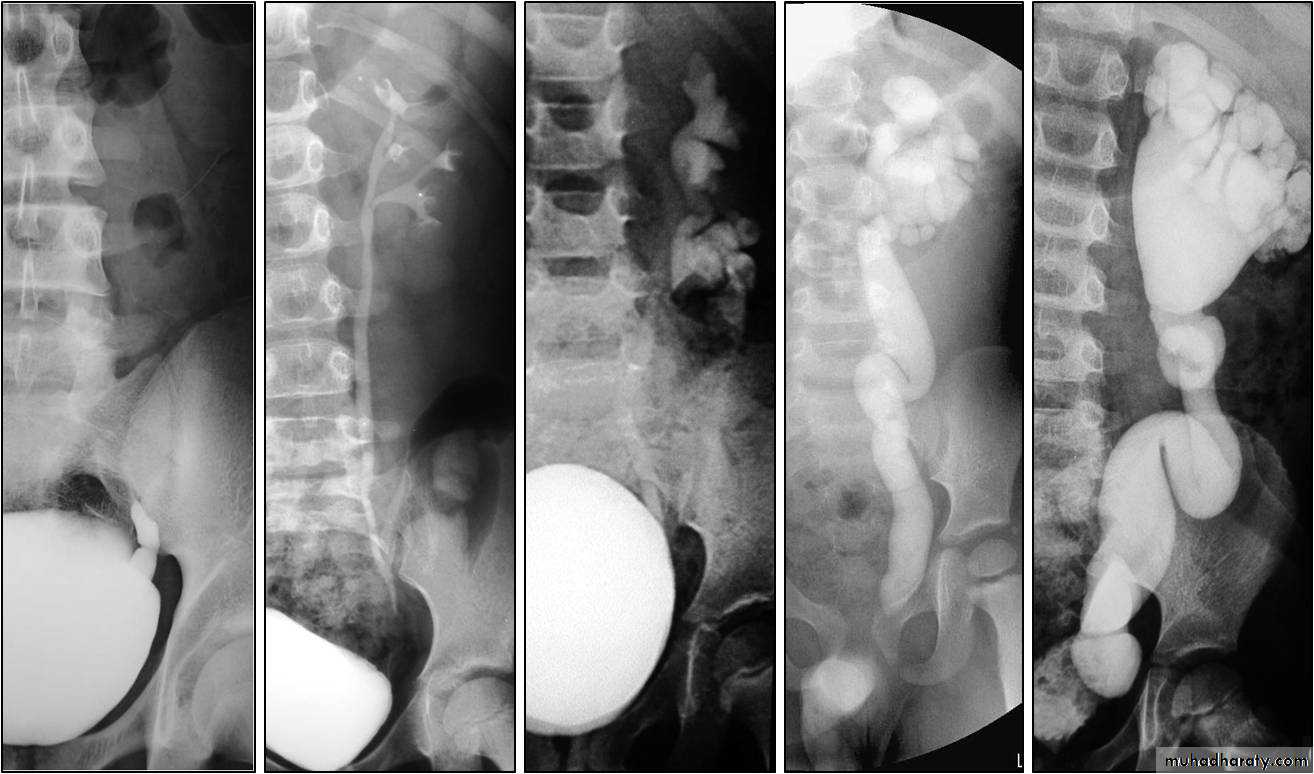

male &female reproductive tractsmammogram

genital tract and mammogram